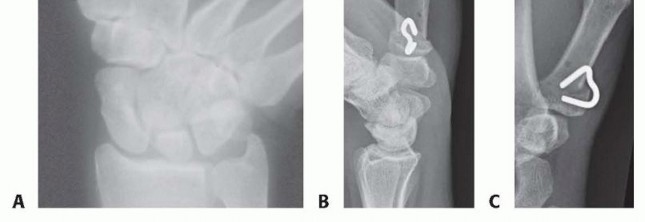

TECH FIG 1 • A. Radiograph showing planned osteotomy. B,C. AP and lateral postoperative thumb radiographs. Use a microsagittal saw to score the metacarpal 1 cm distal to its base transversely, but do not make a complete cut through the volar cortex.Leave a new saw blade in that partial osteotomy site and use a second blade about 5 mm distal to the first cut at an angle of 30 degrees so that the two blades intersect at the volar cortex.Remove the wedge of bone, extend the distal metacarpal and compress it against the proximal fragment, and place one 11 × 8 staple (OSStaple, BioMedical Enterprises, Inc., San Antonio, TX).Typically, I maintain the reduced position of the metacarpal while my assistant predrills and then places the staple (TECH FIG 1B,C).Perform a layered closure of the periosteum and skin and place an overlying thumb spica splint.1. Extension Osteotomy with Kirschner Wire and Tension Band FixationThe technique is as described for staple fixation except for the use of Kirschner wires.Use a microsagittal saw to score the metacarpal 1 cm distal to its base transversely, but do not make a complete cut through the volar cortex.Leave a new saw blade in that partial osteotomy site and use a second blade about 5 mm distal to the first cut at an angle of 30 degrees so that the two blades intersect at the volar cortex.Remove the wedge of bone and use a 0.045-inch Kirschner wire to place a transverse hole on either side of the osteotomy.Pass a 22-gauge wire radial to ulnar and ulnar to radial.Place a 0.045-inch Kirschner wire retrograde through the distal osteotomy site, exiting out the ulnar aspect of the thumb, and compress the osteotomy by extending the distal metacarpal.With an assistant maintaining compression, tighten the wire, cut it, and bend it beneath the thenar musculature. Then advance the Kirschner wire anterograde.Cut the Kirschner wire external to the skin to facilitate removal, and repair the periosteal origin of the thenar musculature with absorbable suture.P.1059